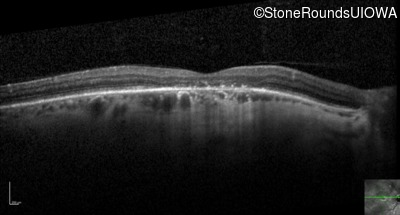

Optical Coherence Tomography - Left - 20/32 -1

Exemplar / OCT Stack

OCT Stack